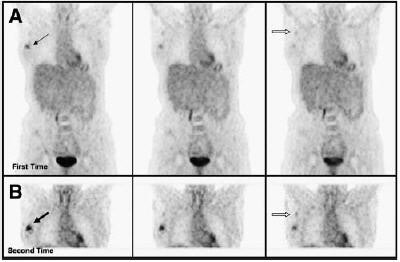

| Patient with invasive ductal carcinoma of right breast was examined with dual-time-point PET. (A) Coronal slices in top row were obtained at first time point. (B) Corresponding images in bottom row were acquired at second time point. Images in both sets clearly show primary lesion. However, intensity of uptake was substantially higher on delayed images. In addition, axillary lymph node metastasis was faintly visualized on first set but clearly demonstrated on second set. Measured SUVmax1 of lesion in first image set was 2.2 (thin black arrow), whereas that of second set was 2.6 (thick black arrow). Percentage increase in SUV of the lesion was 18.2%. SUVmax1 of metastatic right axillary lymph node was 1.0 in first set (open arrow in A) and increased to 1.1 in second set (open arrow in B). Surgical pathology confirmed 2.5-cm invasive ductal carcinoma with axillary metastasis. Copyright © by the Society of Nuclear Medicine. |

In the subgroup of invasive cancer patients, the team found an 8.6% increase in maximum SUV between the two scans for those tumors greater than 10 mm and a 6.5% increase in tumors between 4-10 mm. Invasive ductal tumors had an 8.1% increase, invasive lobular tumors showed a 10.5% increase, invasive mixed tumors had a 9.3% increase, and one medullary tumor demonstrated a 19.4% maximum SUV increase.

The visual results demonstrated 90.1% sensitivity for invasive cancers greater than 10 mm; 82.7% sensitivity for detecting invasive cancers 4–10 mm; and 76.9% sensitivity for detecting noninvasive breast cancer. Dual-time-point PET was true-positive for 99 lesions, indeterminate for 7, and false-negative for 17 lesions. The researchers noted that by visual assessment, most lesions became more intense on delayed scans.